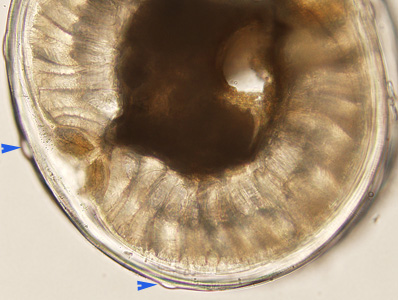

A 27-year-old man had worms excised from his eyelid and chest at a health care facility in Canada. The patient had traveled to Sudan two years earlier, but had not traveled since then. The worms were sent to the DPDx Team for diagnostic assistance. The worm which was removed from the eyelid (Figure A) measured 55 mm in length. Figures B-D show the anterior, middle, and posterior portions of the same worm, respectively, at 100x magnification. A thin cross-section was made with a scalpel at approximately mid-body and examined. Figures E and F show what was observed at 100x and 200x magnification, respectively, of the cross section. What is your diagnosis? Based on what criteria?

Figure F